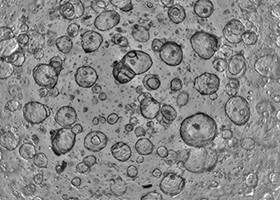

Intestinal organoids

Image Credit: Molecular Devices UK Ltd

They are derived from biopsies of histologically normal duodenal mucosa and reproduce healthy intestinal epithelium.

Intestinal organoids

Image Credit: Molecular Devices UK Ltd

3D tissue models called intestinal organoids replicate the features of the intestinal lumen and the surrounding intestinal epithelium.

Intestinal organoids are valuable for researching intestinal cell biology, regeneration, differentiation, and disease phenotypes, including the effects of certain mutations, the microbiome, or the inflammation process, because of the cell composition and organization of the epithelium.